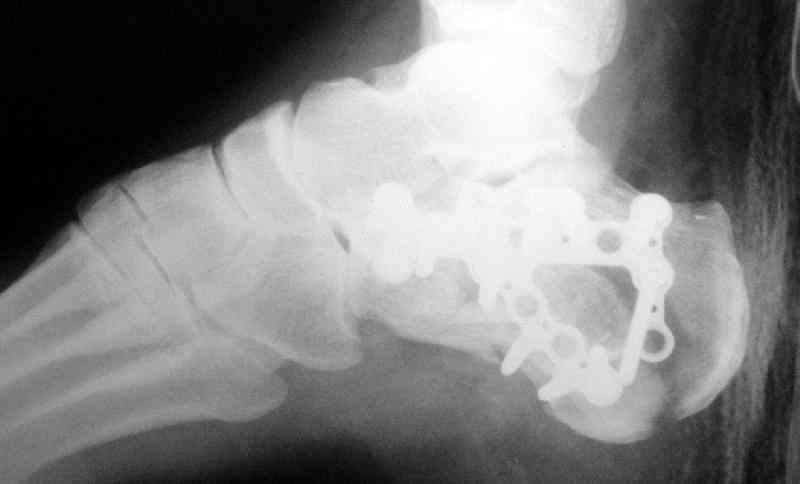

Re: Перелом пяточной кости

Открытый и закрытый способы лечения.